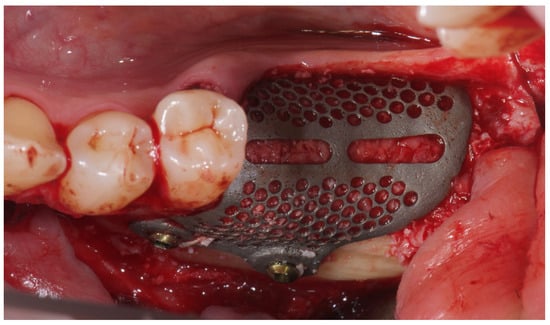

A buccally advanced crestal incision was made through the keratinized tissue (blade No. 15c), and a full-thickness flap was elevated. Vertical releasing incisions were placed mesially (two teeth away) and distally into the retromolar region. The site was debrided and autogenous bone was harvested using a cortical bone scraper (Safe Scraper, Micross, Meta, Reggio Emilia, Italy). After that, low-temperature plasma sterilization of the mesh was carried out. Subsequently, a 1:1 mixture (Figure 4) of autogenous bone and anorganic bovine bone, with a particle size ranging from 0.25 to 1 mm (1 g [2 boxes of 0.5 g [2 CC]]; A-Oss, Osstem Implant) was placed inside the titanium mesh and it was secured on the defect. The titanium mesh was fixed with two screws (Figure 5). Plasma treatment not only allows for high-level sterilization but also allows for a high level of decontamination, increasing the surface energy and the hydrophilicity of the titanium mesh [].

Figure 5. Titanium mesh placement using metal screws on the buccal cortical bone.